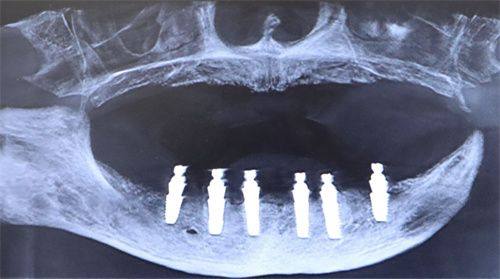

那么,种植牙是如何发挥作用的呢?种植牙利用的是纯钛人工牙根。纯钛这种材料非常特殊,它可以与我们的颌骨发生良好的结合。当把纯钛人工牙根植入到缺失牙的部位后,它就像是一颗种子,会和颌骨紧密地长在一起。这样一来,人工牙根就能稳稳地扎根在口腔里,为上面的假牙提供有力的支撑。就好比盖房子需要一个坚固的地基,种植牙的人工牙根就是假牙的坚实“地基”,让假牙能够像真牙一样发挥功能。

医生会先对患者的口腔进行全方面检查,确定缺失牙部位的具体情况。然后,在局部麻醉的状态下,在缺失牙的位置切开牙龈,暴露牙槽骨,接着在牙槽骨上制备一个合适的孔,将纯钛人工牙根正确地植入进去。这个过程就像是在土地里种下一颗种子,为后续的修复打下基础。整个操作需要医生具备不错的技术和丰富的经验,以确保人工牙根的植入位置和角度正确无误。

当人工牙根与颌骨实现充分的骨结合后,就可以进行末尾一步了。医生会再次切开牙龈,暴露人工牙根,然后在上面依次安放基台、假牙等配件。基台就像是一个桥梁,将人工牙根和假牙连接起来。而假牙的外观和功能都与真牙非常相似,安装好后,患者就可以像使用真牙一样正常咀嚼和微笑了。